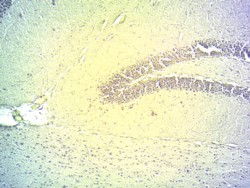

IHC Results Cryo-sectioned Mouse Brain (Hippocampus) shows staining in the granular layer of the dentate gyrus. Recommended concentration: 2-3µg/ml. Data obtained from customer. | |